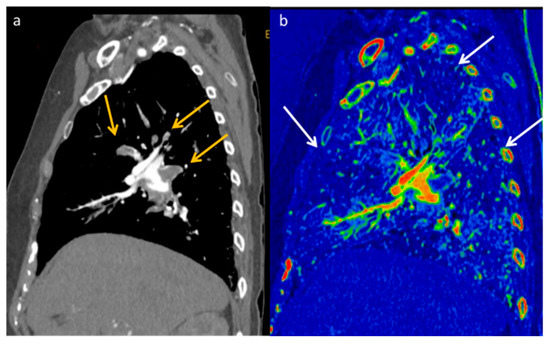

- Dewaguet, J.; Copin, M.-C.; Duhamel, A.; Faivre, J.-B.; Deken, V.; Sedlmair, M.; Flohr, T.; Schmidt, B.; Cortot, A.; Wasielewski, E.; et al. Dual-Energy CT Perfusion of Invasive Tumor Front in Non-Small Cell Lung Cancers. Radiology 2022, 302, 448–456. [Google Scholar] [CrossRef] [PubMed]